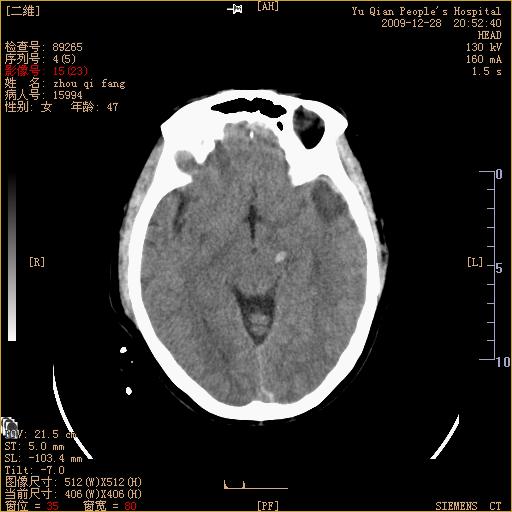

头部外伤后1天   请看看左侧丘脑外侧原是否为小血肿?(两天表现大致相仿。)谢谢

左颞叶前外部见片状挫裂伤,左丘脑小血肿;颅板下见多发小片状血肿影,两侧额部见少量蛛网膜下腔出血,

左额叶颅内板下也有一高密度灶。。。考虑多发小灶性出血(挫裂伤)。。。复查后再定

不好定。同时左侧裂池形态异常,左侧豆状核点状高密度,第四幅右额叶稍高密度影,最后一幅左额叶颅骨内板下方小片状高密度影。复查。